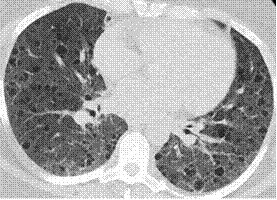

干燥综合征(SS)是不太容易鉴别诊断的,临床上因为干燥综合征引起肺部囊性改变的情况比较多,注意具有多种病理类型。

图:干燥综合征患者LIP + 淀粉样变